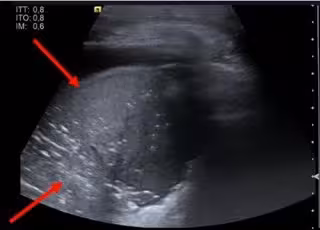

Imagen incluida Suplemento COVID 19 EuroEco

Y es que, los pacientes con Covid-19 presentan un patrón ecográfico característico: adelgazamiento de la línea pleural con irregularidad de la misma; múltiples líneas B con variabilidad de patrones; consolidaciones pulmonares; aparición de líneas A durante la fase de recuperación; y derrame pleural infrecuente.